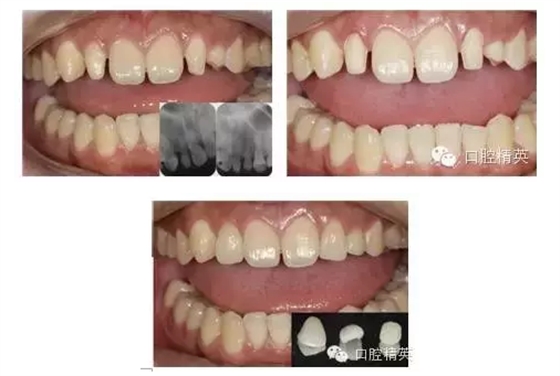

這個患者也是一個關(guān)閉間隙的病例,由于他是一個商場的中層管理,所以他就說,想把兩個中切牙之間的縫進行一些修復處理,他原來也是做樹脂粘結(jié)的,老掉下來,所以他就說能不能有一個永久的方法,因為考慮他的間隙要大一些,差不多得有1.5個毫米左右,所以我們考慮就是做4個前牙的全瓷貼面,這樣以后我們把間隙給每個牙上都分一些,這樣以后我們的前牙會做的更加協(xié)調(diào)一些,不會顯得兩個中切牙很大。下面是我們做一個模型分析,就是說我們在取到一個模型,然后我們在模型上用簡體蠟關(guān)閉間隙,把這個四個上前牙的外形雕出來,來進行一些排牙試驗,看一看把這個牙做多大,貼面做多大合適。右圖是我們牙體預備以后,就是四個牙進行了牙體預備,然后采用一個開張術(shù)的處理。這面是修復完成以后的,從圖上看,第一個我們的間隙基本完全關(guān)閉,第二個顏色來看,四個貼面的顏色和鄰牙的顏色是比較相象的,如間隙均勻的分在了四個前牙上,所以四個前牙的形狀也是比較協(xié)調(diào)的,患者也是非常滿意的。